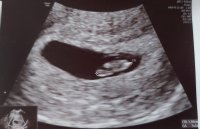

Fikk høre hjertet også- veldig deilig!